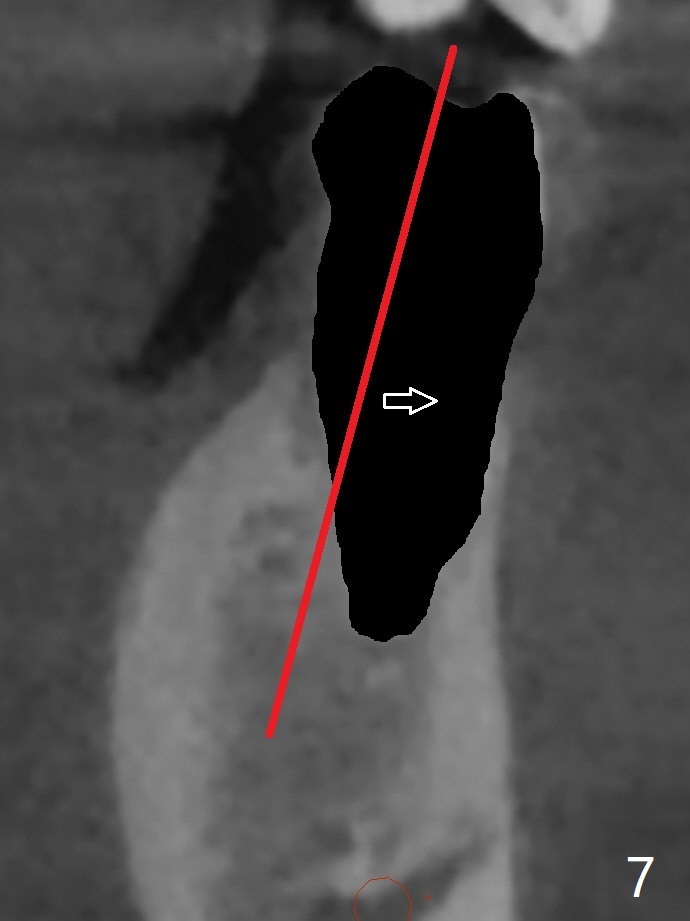

A 40-year-old man with #18 missing and #31 residual roots just fractures the tooth #20 (Fig.1). After discussion, he agrees to have implants at #18 and 20 first. To prevent buccal drifting of osteotomy and implant at #20, the implant will be placed lingual, but it does not contact the lingual plate (Fig.2-4). Traditionally, the whole tooth needs to be extracted (Fig.5,6) before initial osteotomy (Fig.7 red). The latter has tendency to drift buccal because of the lingual slope (Fig.7 arrow). To prevent the drifting, the crown of the tooth is removed (Fig.8). A guide is fabricated with 12 mm offset so that after bone trimmer (Fig.9 pink), the following drills have more contact with metal sleeve. Furthermore the drills will have less chance of buccal shifting because of the presence of the root.